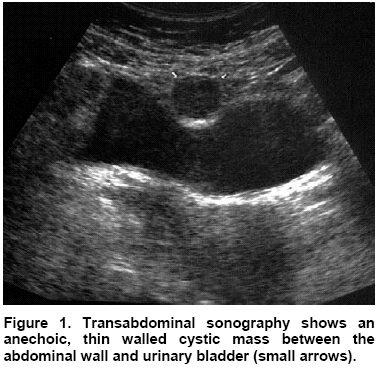

Urachal cyst

Urachal cyst

Urachal cyst

Urachal fistula

Urachal fistula

What is a urichal fistula?

Urachus doesn't close and belly button leaks urin